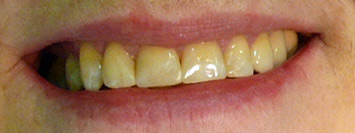

prije